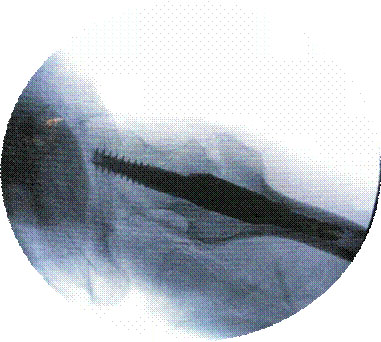

经皮穿刺椎体成形术

优点:微创,迅速解决老年骨质疏松性骨质疼痛。

经皮椎体成形术(PKP、PVP)治疗老年骨质疏松性骨折

优点:损伤小、见效快、安全性高。可以早期下床。